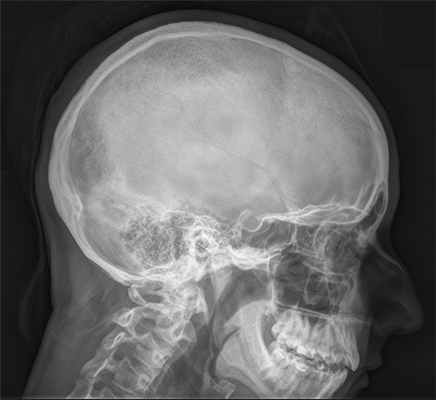

Турецким седлом называется анатомическая область в средней части черепа, напоминающая своей формой седло (этим и обусловлено название). В углублении седла располагается железа внутренней секреции – гипофиз, отвечающий за синтез ряда важнейших гормонов. Так как турецкое седло – костное образование, информацию о его состоянии можно получить с помощью рентгенологического исследования. Востребовано это исследование в гинекологической и нейрохирургической практике. Цель обследования. Исследование турецкого седла. Показания к исследованию. Детализация строения турецкого седла в случаях недостаточно четкого его изображения на снимках черепа в боковой проекции. Детализация патологических изменений турецкого седла. Подозрение на интраселлярные опухоли. Травматические повреждения турецкого седла. Подготовка к исследованию. Подготовка не требуется. Стандартные условия проведения исследования. Прицельная рентгенография турецкого седла производится в боковой проекции с обеих сторон в латеропозиции. Продолжительность исследования - 10-15 мин.

Рентгенографические снимки турецкого седла позволяют оценить размеры, форму, контуры кости, структуру костной ткани. По ним можно обнаружить:

Многие пациенты перед проведением процедуры желают знать: что показывает рентген турецкого седла? Метод достаточно эффективен и позволяет обнаружить любые патологические процессы, развивающиеся в области этой анатомической структуры. Рентгеновские снимки позволяют увидеть костную ткань, что даёт возможность определить не только форму, но и размеры наряду с контурами анатомического образования. В процессе расшифровки полученных данных врач сравнивает их с параметрами нормы по ряду критериев и делает соответствующий вывод.

Для того, чтобы определить размеры и форму турецкого седла по отношению к размерам и форме черепа, проводят боковую левую и правую обзорную рентгенографию черепа. Помимо этого, съёмку проводят в следующих проекциях в прямой лобно-носовой и прямой задней. Пациент принимает положение стоя возле рентгеновского аппарата, поворочиваясь лицом, спиной и боком, после чего проводится съёмка.

Что показывает снимок черепа?

По рентгеновским снимкам турецкого седла можно судить о его форме, структуре и размерах. Гипофиз также визуализируется на рентгене и о его опухоли могут свидетельствовать следующие признаки:

- местный или полный остеопороз стенок турецкого седла с сохранением нормальной структуры других костных образований;

- местная или полная атрофия стенок турецкого седла (на снимках можно заметить, как истончены стенки);

- местное или полное истончение клиновидных отростков турецкого седла;

- неравномерность контуров турецкого седла с внутренней стороны.

Описание снимка и заключение выполняет специалист-рентгенолог. При этом он определяет состояние стенки, а также форму и размеры турецкого седла. Если на снимке визуализируется опухоль, врач описывает её размеры, структуру и локализацию.

Рентгенография иногда может показать такую патологию, как «пустое турецкое седло». Признаки её могут быть следующими:

- дно во фронтальной плоскости симметрично;

- вертикальное увеличение седла замкнутой формы;

- двухконтурное дно на сагиттальном снимке.

Критериями для интерпретации рентген-снимков служат нормы размеров костей турецкого седла:

- вертикальный размер – от 7 до 12 мм;

- сагиттальный размер – от 9 до 15 мм.

- Соотношение высоты турецкого седла с его длиной. Этот индекс у взрослых должен быть больше 1, а у детей – меньше. Определение данного индекса даёт возможность понять, есть ли отклонение в строении и структуре гипофиза.